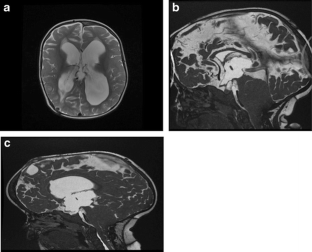

Fig. 4